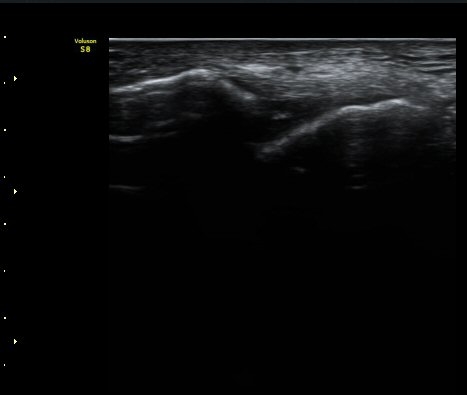

Àü°Å°ñºñ°ñÀδë Á¾´Ü¸é°Ë»ç¿¡¼­ ÀδëÀÇ ÀüÃþÆÄ¿­°ú ºÎÁ¾ÀÌ °üÂûµÈ´Ù(±×¸² 3, 4).

°ÇÃø(±×¸² 5)°ú ºñ±³ÇØ º¸¸é È¯ÃøÀÇ ÀÎ´ë ¼Õ»óÀÌ ¶Ñ·ÈÇÏ´Ù.